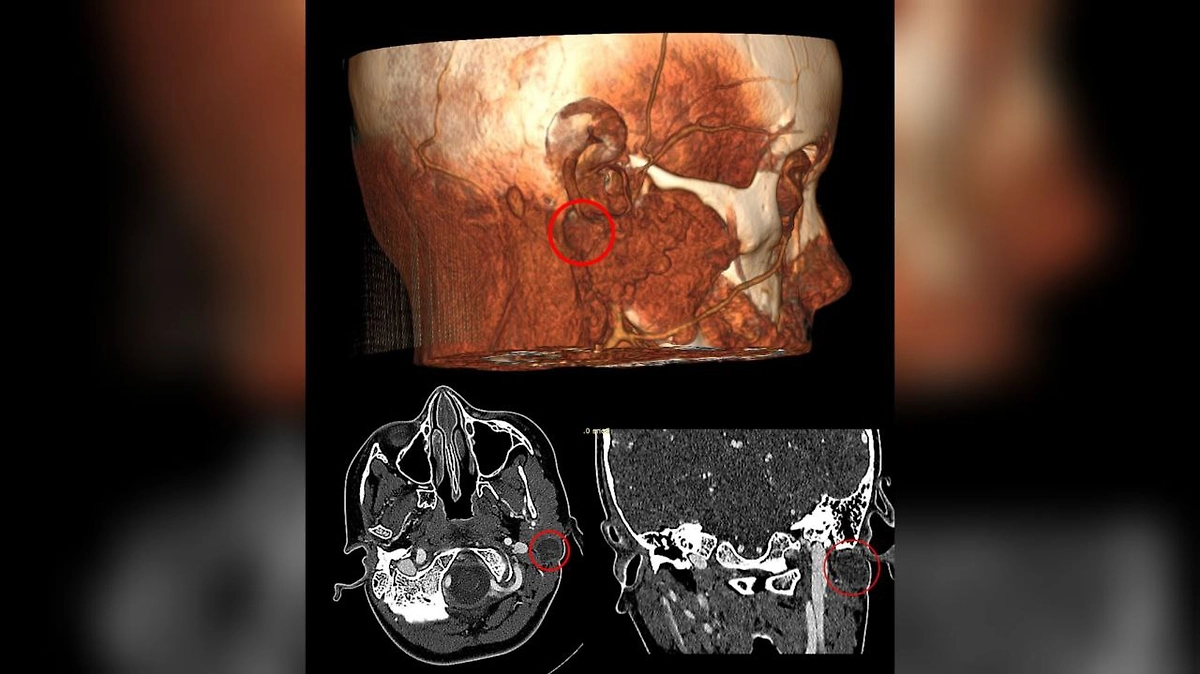

Хирурги отделения челюстно-лицевой хирургии Российской детской клинической больницы (РДКБ) Минздрава России провели уникальную операцию по удалению кисты первой жаберной щели у семилетней девочки из Сыктывкара. Это врождённое образование, встречающееся реже, чем в одном случае на миллион, в течение трёх лет вызывало у ребёнка постоянные воспаления, нагноения и сильную боль.

Как пояснил заведующий отделением, д.м.н. Александр Кугушев, киста формируется из-за аномалии эмбрионального развития и, выстланная эпителием, постоянно продуцирует секрет, что создаёт очаг для инфекции. Основной сложностью для хирургов было её расположение: образование плотно прилегало к лицевому нерву и крупным сосудам. Повреждение нерва грозило необратимой потерей мимики — по мировой статистике, такое осложнение возникает у 20% пациентов.

Московские врачи провели «ювелирную» операцию. Киста была удалена единым блоком через небольшой разрез, скрытый в естественной складке за ухом. Хирургам удалось не задеть ни нерв, ни сосуды, полностью сохранив функции лица и не оставив видимых косметических дефектов.